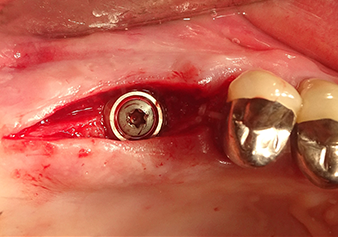

После промежуточного контроля (рис. 4) был проведен еще один этап подготовки (рис. 5). За тем, с помощью гидравлического инструмента Z35P мембрана была поднята в нужное положение (рис. 6 и 7). Далее, следовала дальнейшая пьезохирургическая подготовка ложа для имплантата, завершенная с помощью ротационного бора и лопаточной фрезы до диаметра имплантата 4,8 мм. Перед установкой имплантата под мембрану Шнейдера был введен аугментационный материал (размер частиц около 0,8-1,6 мм) (рис. 8).

Имплантация и протезирование

Situation after insertion of the implant

Рис.9: Ситуация после установки имплантата (длина: 10 мм, ортопедическая площадка: 6,5 мм) непосредственно перед наложением швов